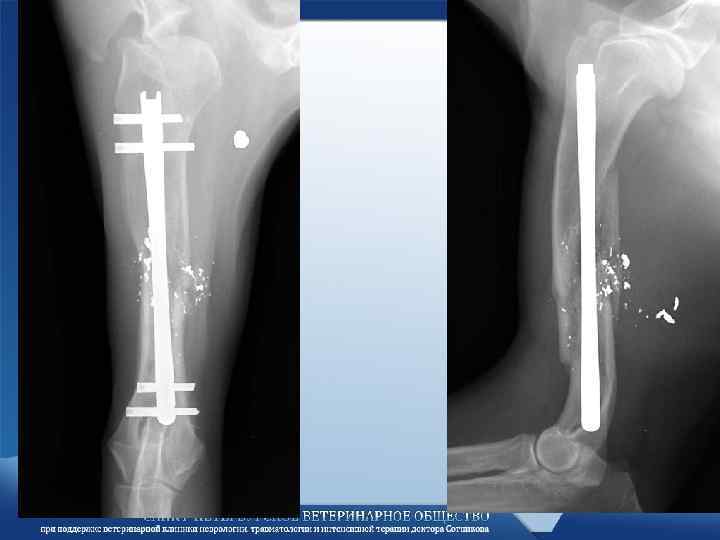

Интрамедулярный штифт Интрамедулярный штифт

Интрамедулярный остеосинтез • Фиксация перелома интрамедулярным штифтом с запирающим винтом. – Такой фиксатор успешно Интрамедулярный остеосинтез • Фиксация перелома интрамедулярным штифтом с запирающим винтом. – Такой фиксатор успешно противостоит всем силам действующим на перелом.